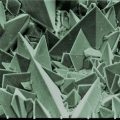

There is a truism in the sociology of occupational knowledge: “If all a doctor has is a hammer, then everything becomes a nail”. All modern medicine relies on overkill dosages of drugs or surgery as the standard of care (Jennifer Daniels, MD, The Lethal Dose, 2013). There are no drugs or surgery that can alleviate the symptoms of poisoning from a natural pesticide found in plant foods but also produced in the liver. With this professional void, treating oxalosis has mainly been left to nutritionists. So, if you ask a nutritionist about oxalates, you will get a predictable answer to reduce oxalates in your diet. This is insufficient because most oxalates are produced by poor metabolism in the liver. Oxalate is a natural pesticide found in plant foods, but also is internally produced mainly from fungus and vitamin C (see How Oxalates Ruin Your Health). Oxalosis manifests as a syndrome of three main symptoms: oxalate crystals in tissues and kidney; histamine, mucous attack in nasal passages; and pseudo-gout mainly from acidity and eating cooked meat.

Only after hitting a wall of brain fog, fatigue, pseudo-gout, nasal mucous attacks, extreme lack of thyroid hormone, pins and needles on the bottom of my feet, and crystals popping from my eyes, did I seek medical consultation for these symptoms. After several futile consultations, I found that doctors don’t know anything about oxalates. Finally, a naturopath doctor gave me an office blood blot test and stated I had oxalates. The only knowledgeable people I could find about what to do with oxalates was from a self-help group at TryingLowOxalates.io and the Hormones Matter.com website. I won’t bore you further with my medical system merry-go-round story that all those with oxalosis go through and instead will try and relate what I have learned to date, albeit all errors are my own.

First, I learned that calcium is needed as a co-valent chemical binder to oxalate before meals to eliminate oxalate through the bowel or oxalic acid through with urine through the kidney. Secondly, I learned that plant foods like spinach, almonds, chocolate, and soy and were loaded with toxic levels of oxalates, a natural pesticide that protects plants from insects, worms, and herbivores. I also learned that high doses of synthetic Vitamin D (10,000 mg/day as a steroid) without Vitamin K2, could also lead to kidney stones and oxalosis. An iron deficiency may come into the picture as discussed below.

He goes on to argue that toxic blood gets to the lung through the arteries and then permeates into the lung by cellular membrane diffusion in balloon-like alveoli sacks. For oxygen to get distributed throughout our body it first needs a transporter of red blood cells to carry oxygen-binding molecules called hemoglobin. Dietary iron is the building block of hemoglobin and is carried throughout the vascular system to bone marrow which is the farm for making red blood cells. Oxalates can bind to iron and subsequently lead to chronic anemia. So, oxygen production begins in the gut not the lung. Iron anemia is a predictor of poor outcome from lung infection. The oxygenated red blood cells then are carried throughout the body by the flow of blood.